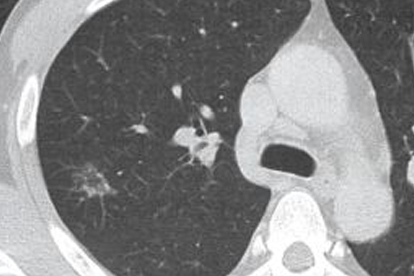

南京市第一医院呼吸与危重症医学科在肺癌早期诊断和综合治疗方面具有特色优势。医院开展CT引导下肺穿刺活检、EBUS等技术,为肺癌患者提供诊断。科室注重多学科协作,制定个体化的治疗方案。